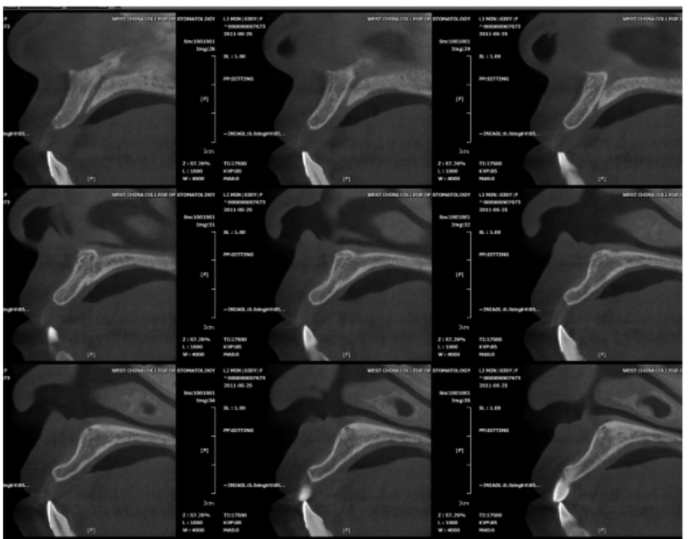

同一个患者前牙区的牙槽骨在不同的位置层面其牙槽骨形状也不一致;

图10 术前CBCT片矢状位显示在不同的层面上颌前牙区的牙槽骨形状不一致

图11 术前CBCT片矢状位显示在不同的层面上颌前牙区的牙槽骨形状不一致,牙槽窝未完全恢复